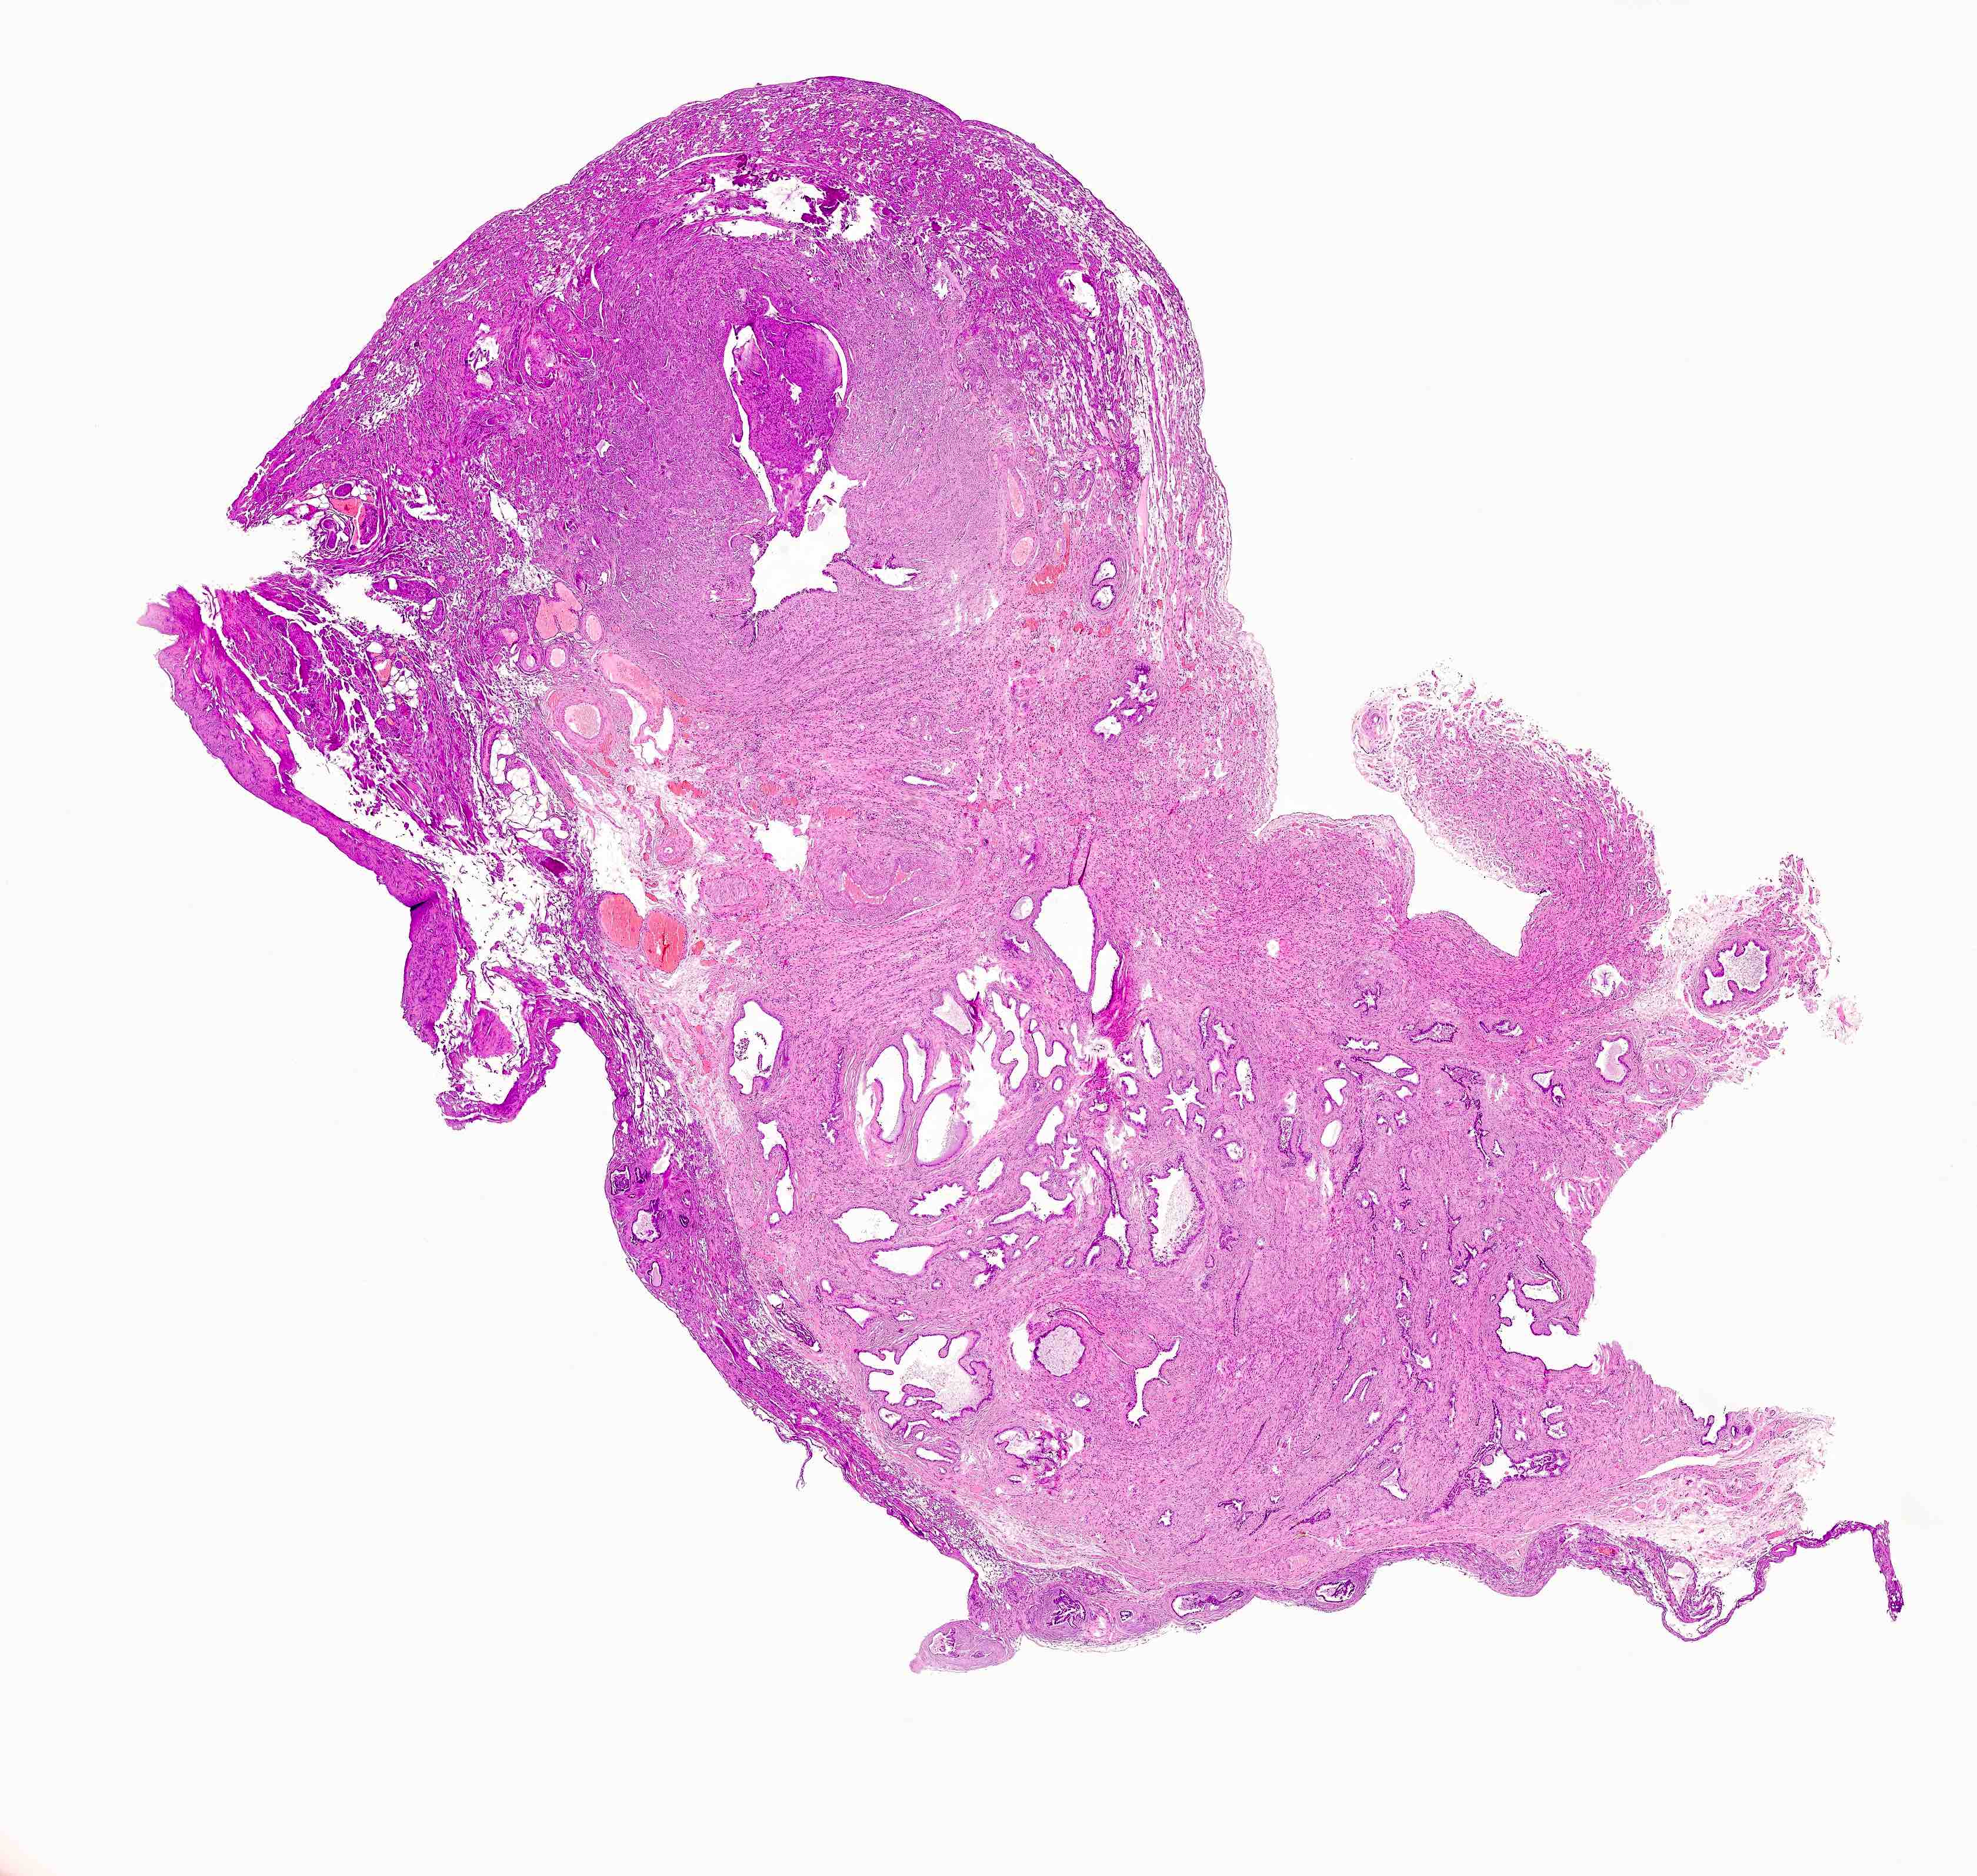

Microscopic (histologic) description

- Regularly spaced glands lined by normal appearing tubal epithelium surrounded by smooth muscle or fibrous tissue

- Tubal lumina are true diverticula that communicate with the central tubal lumen but do not connect with the serosa

- Glands can become cystically dilated (Am J Clin Pathol 1951;21:212)

- No significant atypia, scarring or associated inflammatory / stromal response

- Absence of endometrial stroma differentiates this entity from tubal endometriosis

Microscopic (histologic) images